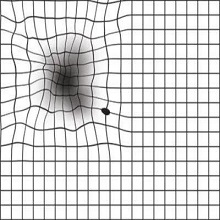

| Акутни глауком спада у групу најургентнијих стања у офталмологији, тако да захтева брзу дијагнозу и терапију. |

Процењује се да око 80 милиона људи широм света има глауком а 111,8 милиона људи има предиспозицију да добије глауком до 2040. године. У Србији је претпоставка да од ове болести болује око 100.000 људи јер не постоје прецизни подаци о оболелима јер глауком није болест која се обавезно пријављује. |

Током прошле године у Очној болници Опште болнице Панчево обављено је близу хиљаду операција катаракте. Тренутно је на листи око 200 пацијeната који ће бити оперисани у наредна три месеца. |

| Светски дан вида обележава се сваке године 14. октобра с намером да се упозори на проблеме слепих и слабовидих особа и особа са оштећеним видом, те да допринесе решавању тог глобалног здравственог проблема. Чуло вида је важно за живот сваког човека и представља изузетно софицтициран орган који може да се пореди са фотоапаратом. |